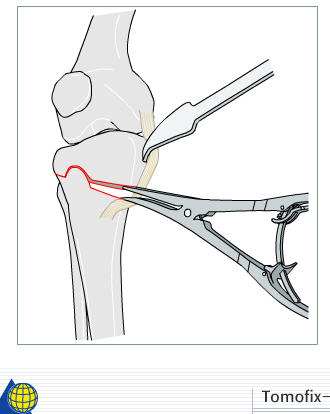

I prefer a medial opening wedge. Currently I prefer the tomofix system by synthes. Its instrumentation allows "dialing in" the correction nicely, and the fixed angle construct provides excellent stability. A few other companies have similar systems, Arthrex for example. Trying to hinge the correction on intact lateral cortex (1 cm.) is key to preserve stability.

The nonunion/hardware failure rate is substantially higher when the lateral cortex is breeched. Fibular osteotomy not required.

Attached is a screen capture from the AO foundation website which has an excellent training module on performing an opening wedge HTO. It shows from preop planning to intra-op techniques. It is helpful even if you don't use their product to perform the procedure. Certainly it is not mandatory to use any osteotomy system to obtain and secure a well done osteotomy - im not sure what instrumentation you have access to.

4) if the correction is large( over 8 deg) or any cracks appear, or you put the limb axis in or beyond the neutral plane, so that the osteotomy is in tension rather than compression, then use a strong device( e.g. a Tomofix plate) rather than a minimal invasive device( e.g. a Pudu plate) - have both available if you're not sure, as the actual kit to do the osteotomy is a bit better on the Pudu set